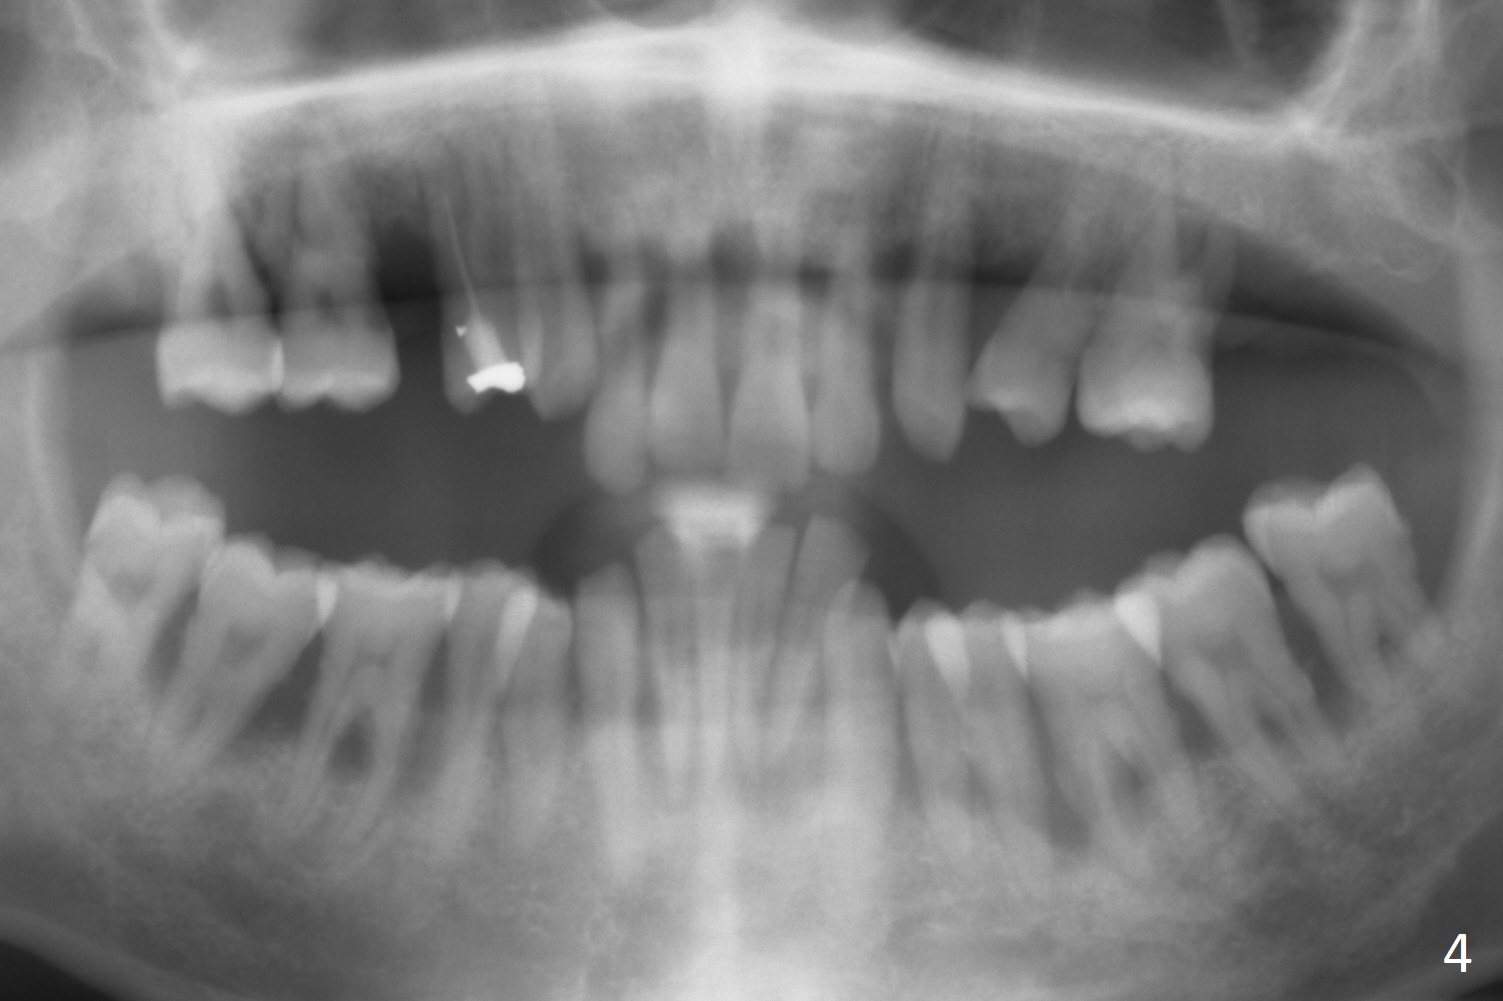

A 36-year-old man (ex-smoker) has advanced chronic periodontitis (Fig.1-5). His chief complaint is "I cannot chew on the right side now because of pain (Fig.1: #3 abscess <) and the bottom front teeth are loose (Fig.2,5: #23-26)". He has not masticated on the left side because of the mobile teeth. Due to finance, implants will be placed at #3,4 (Fig.12), 23 and 26 at the appointments of scaling & root planing.

Class II Division II malocclusion (Fig.2,6) will make it difficult to restore #23-26 implant-supported FPD. Although the teeth #7-10 may need to be replaced later (Fig.7,8), enameloplasty will be conducted for #7-10 (Fig.9 white area; Fig.12 black circles (gross reduction)) prior to #23-26 extraction and implant placement (Fig.10). To be flexible in restoration (angulation) and possible future hybrid denture, 2-piece narrow implants will be placed (3.0 or 3.3 mm) instead of 1-piece ones. In fact CBCT shows that the narrowest regular implant (3.8 mm) can be placed in the lower anterior region (Fig.13-15).